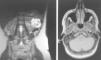

En el electrocardiograma se objetiva taquicardia sinusal a 120 lpm, sin alteraciones en la conducción auriculoventricular ni intraventricular, ni alteraciones en la repolarización. En el análisis practicado destaca NTproBNP de 2.948,7pg/ml (Valores normales (VN): 0-125pg/ml) y un CA 12,5 de 180,5 U/ml (VN 0-35 U/ml), ambos marcadores de congestión y de conocido valor pronóstico en la insuficiencia cardíaca. No se encuentran alteraciones destacables en el resto de parámetros estudiados. La función tiroidea, el perfil lipídico y los marcadores de autoinmunidad son normales. En la radiografía de tórax se observa una silueta cardiaca de tamaño normal con un patrón reticular bilateral sugerente de edema intersticial. Tras los hallazgos descritos, se realiza una ecocardiografía transtorácica, en la que destaca una ligera dilatación ventricular izquierda con FEVI (Fracción de eyección del ventrículo izquierdo) moderadamente deprimida (45%) (VN para su edad 60%) y una insuficiencia mitral grave grado IV/IV con válvula de aspecto normal (fig. 1A).

2A) RM abdominal axial. Tumoración quística heterogénea en riñón izquierdo, de 7,6×6,2cm de diámetro.

2B) RM cerebral. Lesiones hipercaptantes, situadas en el hemisferio cerebeloso izquierdo, una de unos 5mm y la otra más periférica de 3mm, que corresponden a pequeños hemangioblastomas cerebelosos.

Estos resultados indican la presencia de feocromocitoma y justifican el cuadro clínico. Con este diagnóstico de sospecha en contexto de síndrome de von Hippel Lindau, la paciente pasa a cargo de Servicio de Endocrinología. Se completa el estudio solicitándose RM abdominal y RM cerebral. En la primera, se objetiva una masa suprarrenal izquierda de 2,3cm de diámetro bien delimitada sugestiva de feocromocitoma (fig. 1B). Del mismo modo se informa de una tumoración quística heterogénea en riñón izquierdo, de 7,6×6,2cm de diámetro, en la glándula pancreática se aprecian numerosas formaciones con señal quística tanto en cabeza, cuello como en cola (fig. 2A). La RM cerebral muestra dos pequeñas lesiones hipercaptantes, situadas en el hemisferio cerebeloso izquierdo, una de unos 5mm y la otra más periférica de 3mm, que corresponden a hemangioblastomas cerebelosos (fig. 2B). Una vez realizado el diagnóstico de imagen se contacta con servicio de Urología para planear el abordaje quirúrgico. Se inicia la preparación preoperatoria con dosis crecientes de fenoxibenzamina hasta alcanzar los 20mg/12h. Posteriormente, la paciente presenta un cuadro de palpitaciones, objetivándose taquicardia sinusal que se controla con propranolol a dosis de 20mg/12h. Una vez alcanzada la estabilidad clínica se decide la intervención quirúrgica. Es intervenida 20 días después practicándose una nefrectomía radical y suprarrenalectomia por vía laparoscópica. La paciente no presenta complicaciones inmediatas, objetivándose una mejoría de las cifras tensionales, así como de las palpitaciones. El estudio anatomopatológico mostró un feocromocitoma y un carcinoma renal de células claras. Se solicita un estudio bioquímico posquirúrgico en el que se objetivó la normalización de las catecolaminas y metranefrinas en orina. Destacar que la paciente no presenta antecedentes familiares y que el análisis genético mediante MLPA (Multiplex Ligation-dependent Probe Amplification) de ADN leucocitatrio mostró que la paciente es portadora de una deleción del exon 3 del gen VHL en heterocigosis, no existiendo dudas sobre su predisposición al síndrome de VHL. Se concluye, dado que los familiares no están afectos, que es una mutación de novo. Posteriormente ingresó en Neurología por hipoestesia en hemicuerpo derecho siendo diagnosticada de hemangioblastoma intramedular (febrero 2011), en seguimiento por neurocirugía. Actualmente, la paciente se encuentra asintomática desde el punto de vista cardiovascular realizándose ecocardiografía de control en la que se objetiva ausencia de insuficiencia mitral y FEVI normal.